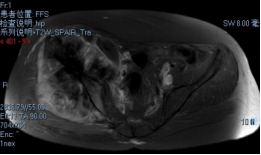

术前影像

穿刺活检提示骨盆软骨肉瘤

日前,安医大一附院骨病骨肿瘤外科胡勇教授团队成功完成一例复杂骨盆Ⅰ+Ⅱ+Ⅲ+Ⅳ区肿瘤切除与3D打印组配式半骨盆假体重建手术。患者为女性,53岁,下腰痛半年余,右侧臀部膨隆,右侧下肢轻度浮肿。右侧髂棘髂窝及臀部可触及巨大肿物,压痛明显,右髋外展前屈活动受限,右侧大腿感觉麻木,右足感觉运动正常。骨盆肿瘤切除重建是骨科专业中难度极大、风险极高的手术。骨盆肿瘤约占原发骨肿瘤的3%~4%,其中以软骨系统肿瘤最为多见,其次为骨巨细胞瘤、成骨肉瘤等,儿童尤文肉瘤亦好发于骨盆。

骨盆恶性肿瘤常潜在发展,由于骨盆位置较深,肿瘤早期很难发现,从第一次出现症状到诊断明确有时需要很长时间,当出现临床症状时,肿瘤体积已较大,因而手术切除相当困难。骨盆肿瘤血供丰富,手术出血多、难度大。另外,骨盆形态特殊,解剖复杂,切除肿瘤的同时,需要重建骨盆结构和肢体功能,技术要求高。